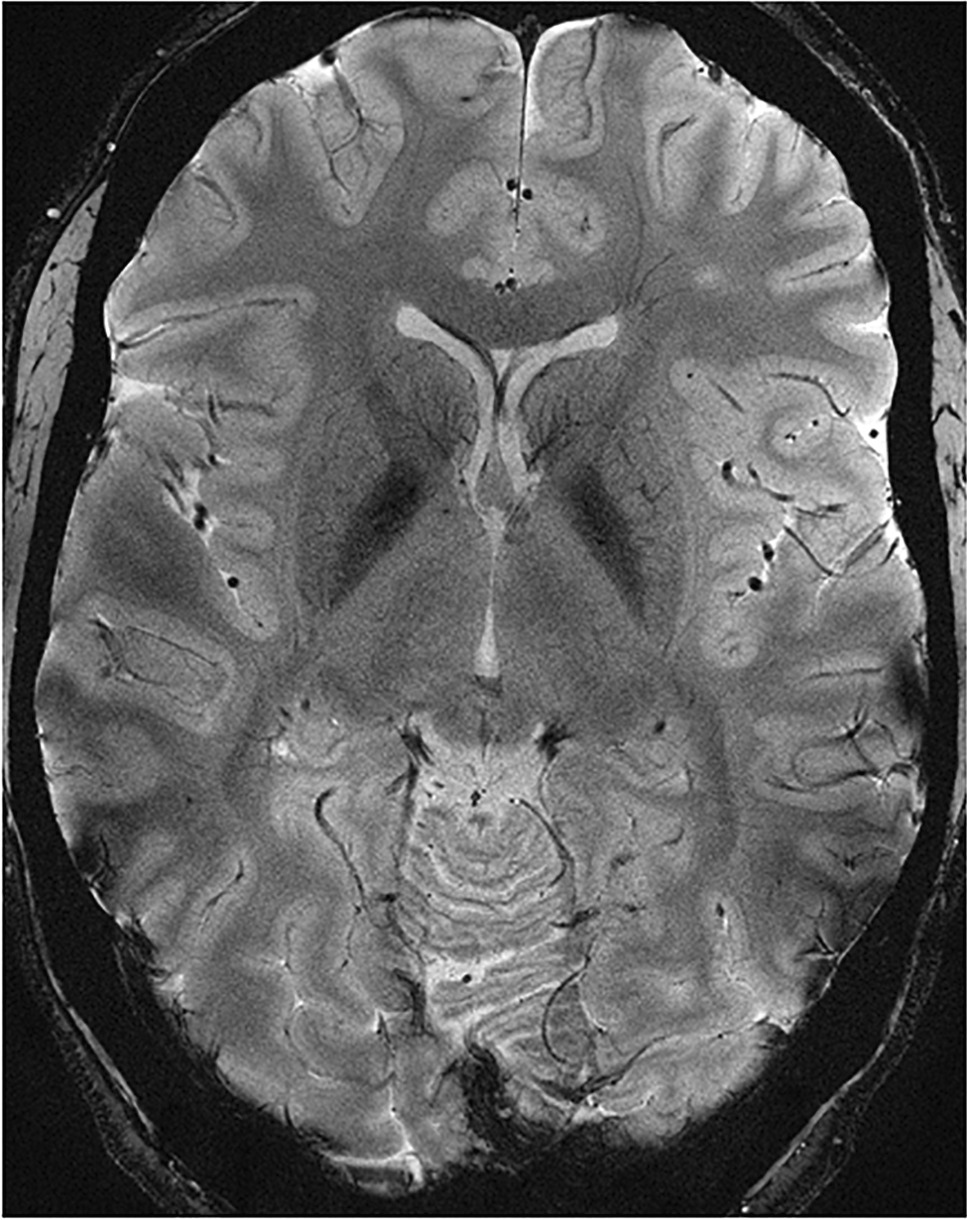

Development of a clinically applicable 7 T and 9.4 T MRI scan protocol for detection of structural abnormalities is part of this study. We created a format for a proposed UHF scan protocol (see Table 2). All sequences will acquire images of the whole brain. This scan protocol allows for the use of normative control data, acquired by Haast et al. [30]. Two dielectric CaTiO3 pads with demineralized water are used to improve the inhomogeneous MRI signal in the temporal lobes. As a preparation, we scanned some controls at 7 T to assess image quality (see Figs. 2 and 3).

Fig. 3

7 T 2D dual-echo GRE (T2*) axial image of a test subject’s cerebrum with a voxel size of 0.3 × 0.3 × 2.0 mm